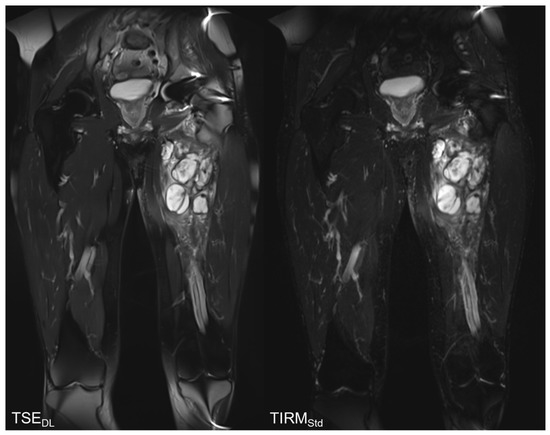

Reduction in Acquisition Time and Improvement in Image Quality in T2-Weighted MR Imaging of Musculoskeletal Tumors of the Extremities Using a Novel Deep Learning-Based Reconstruction Technique in a Turbo Spin Echo (TSE) Sequence

3.4. Qualitative Image Analysis